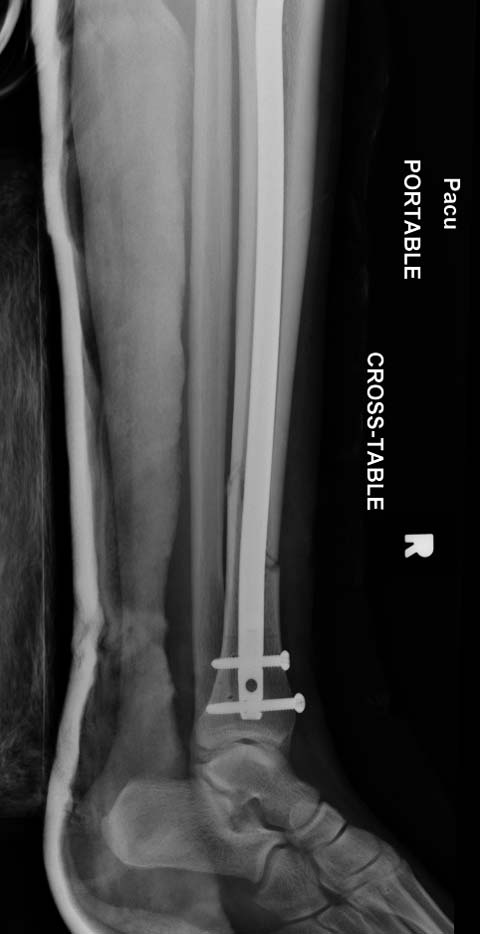

набора гвоздей повлияло на выбор короткого имплантата, имеется угловая и

ротационная деформации. Независимо от локализации, стабильность

создается, когда гвоздь проксимально не глубже 1.5 см (облегчает

удаление) и дистально доходит до epiphyseal scar.

Здесь несколько снимков изолированного перелома большеберцовой с

интактной малоберцовой.  Weber clamp, блокирующие спицы и риминг в

центре канала отрепонировал перелом....